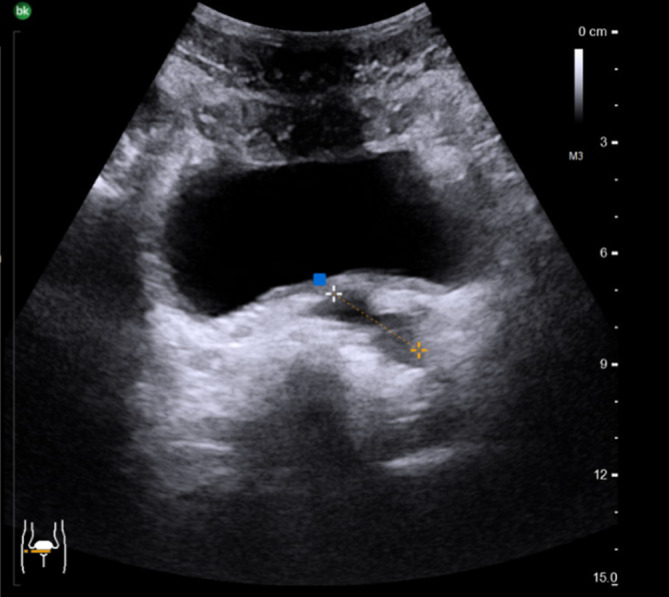

29岁男性原发不孕症2年提出进一步评估。重复精子图显示无精子症和酸性ph值。超声检查显示两睾丸大小和实质正常,但双侧输精管未触及。磁共振显示左侧输精管囊性扩张,左侧精囊扩张。右侧输精管未见。睾丸精子提取(TESE)成功,仅显示精子发生轻微损伤,约翰逊评分为9分。

A 29-year-old man with primary infertility for 2 years presented for further evaluation. Repeated spermiograms showed azoospermia and an acidic pH. Sonographically, both testes showed normal size and parenchyma, but the vas deferens was bilaterally not palpable. Magnetic resonance imaging showed a cystically dilated left vas deferens and a dilated left seminal vesicle. The right vas deferens could not be visualized. Testicular sperm extraction (TESE) was successful and showed only slight impairment of the spermatogenesis with a Johnson score of 9.